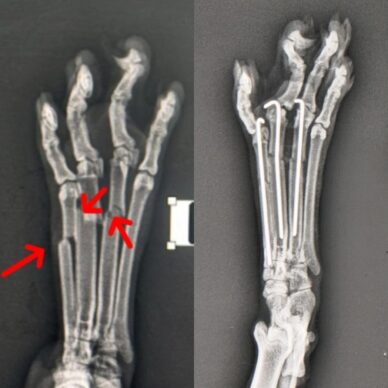

Ortopedi Cerrahi

Kedi ve köpeklerde ortopedi cerrahisinde başarı